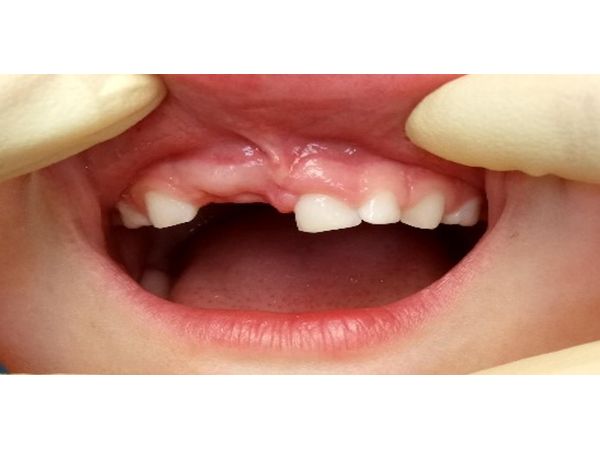

После того как удалось установить контакт с ребёнком, ей сделали анестезию и удалили зубы 51 и 52. На зубы 61 и 62 установили композитную шину. Обработали царапину антисептиком и нанесли кератопластическую мазь.

Через четыре недели пациентке удалили шину и провели рентгенологический контроль: воспаления в области корня зуба 61 не было.

Через два года после травмы, когда девочке исполнилось 7 лет, 61 зуб сменился на постоянный. Постоянный левый центральный резец (зуб 21) и верхние правые резцы (зубы 11 и 12) также прорезались в срок. Они росли в правильном положении, без видимых патологических изменений.